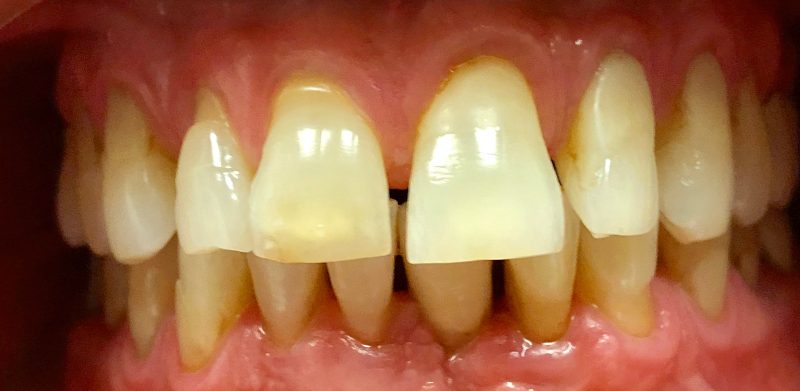

TREATMENT: VENEERS

Patient: Glenn

Before his treatment at Riverside Tooth Co, Glenn had lived for years with large gaps in his smile. These gaps weren’t just a cosmetic issue— they would cause food debris to get stuck in between his teeth, which led to gum inflammation and irritation. From the time he walked into our office, Glenn was excited at the prospect of enhancing his smile. Now that he has well-aligned teeth with no gaps, Glenn can smile with pride and confidence.